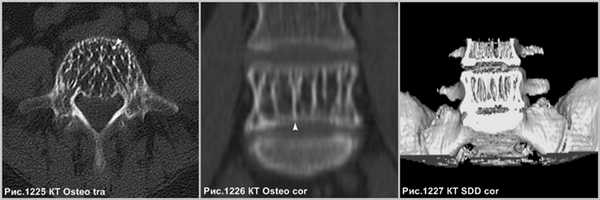

Гипертрофированные вертикальные балки губчатого вещества превосходно видны на КТ (рис.1227 и головки стрелок на рис.1225,1226).

Крупная гемангиома в теле L5 позвонка, распространяющаяся на всё его тело, приводящая к перестройке губчатого вещества кости, с разряжением губчатого вещества и наличием вертикальных утолщенных костных балок (головки стрелок на рис.1222,1223). Гемангиома в теле позвонка, имеющая жировую интенсивность МР-сигнала - ↑сигнал по Т1, с обозначением контура на последовательности в противофазе (головка стрелки на рис.1224), и имеющая выпадение МР-сигнала в режиме Т2 с жироподавлением (стрелка на рис.1224), что соответствует жировой ткани в гемангиоме.